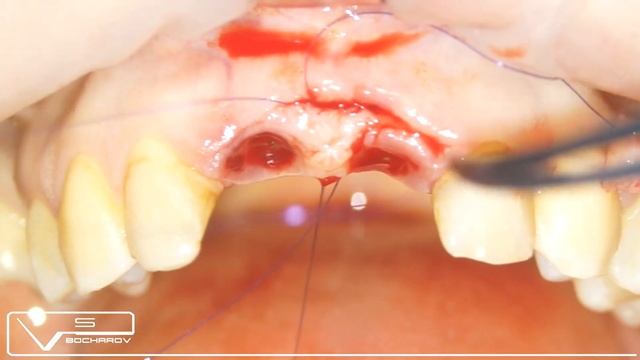

Lateral Window Sinus Augmentation: sequence of piezoelectric surgery tips смотреть онлайн

04:54

Lateral Window Sinus Augmentation: sequence of piezoelectric surgery tips

Лифтинговые Перспективы 17 просмотров